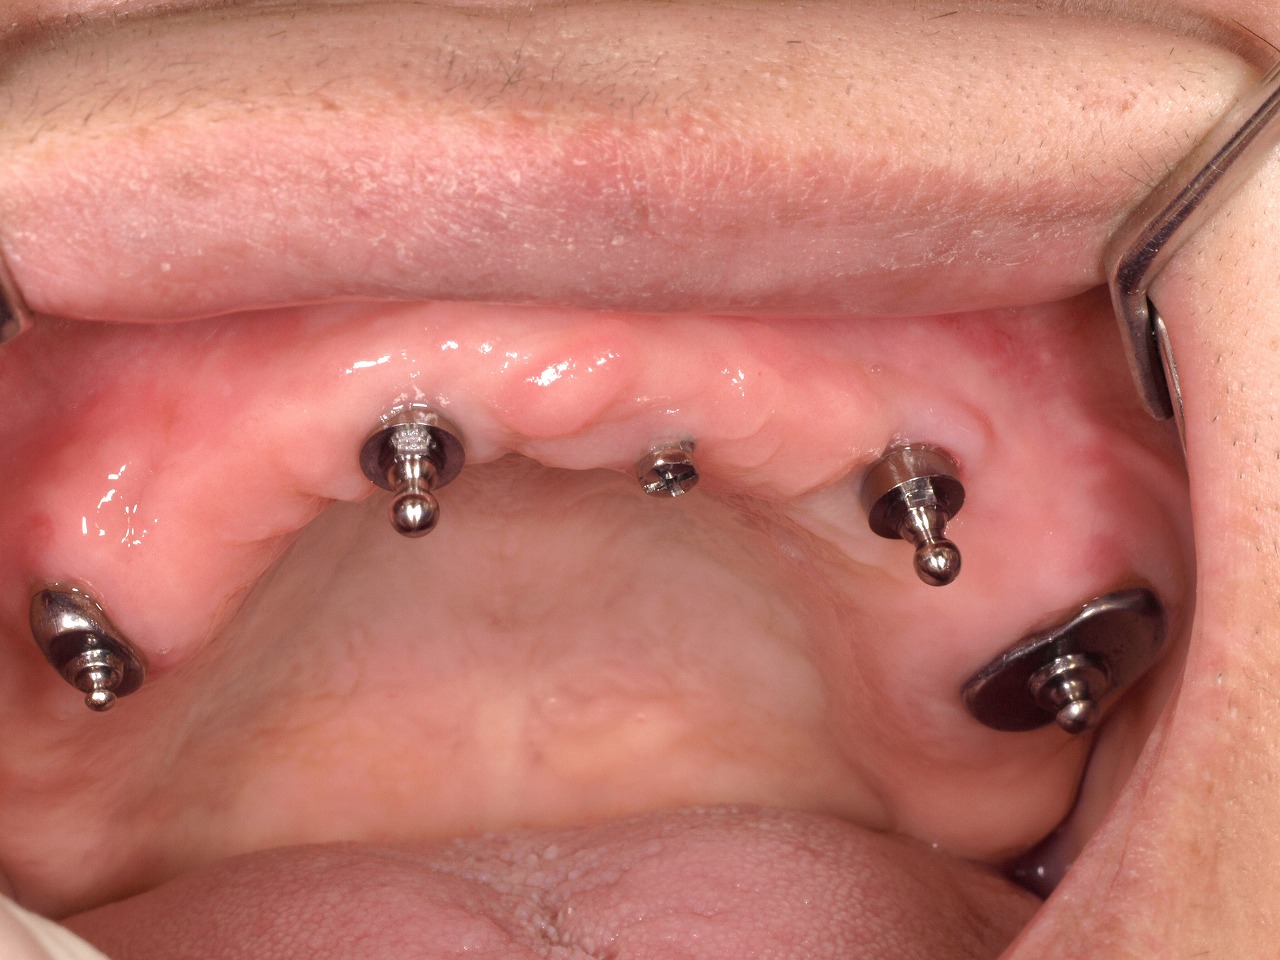

インプラントを用いたオーバーデンチャータイプの最終治療義歯の流れ|お知らせ |広島市安佐南区の歯科医院 インプラントを用いたオーバーデンチャータイプの最終治療義歯の流れ トップ お知らせ・ブログ お知らせ インプラントを用いたオーバーデンチャータイプの最終治療義歯の流れ インプラントを用いたオーバーデンチャータイプの最終治療義歯の流れ 術後のパノラマになります 口腔内です インプラントも用いた4本の0-リング 治療義歯 内面に0-リングを1つずつ確実に設置していきます この入れ歯だと数年後破折してしまうので、金属フレームが入った 入れ歯の再作成が必要となります Web診療予約 初めての方へ 選ばれ続ける理由 院内設備について 歯が痛いしみる一般歯科 歯がぐらぐらする歯周病 健康な歯を保ちたい予防歯科 子供の虫歯予防をしたい小児歯科 銀歯をセラミックに審美歯科 白い歯を目指しませんか?ホワイトニング 矯正専門医がいるので安心矯正歯科 抜けた歯を補いたいインプラント・入れ歯 医院案内 スタッフ紹介 メリィハウス歯科クリニックオフィシャルホームページ ラベンダー歯科クリニックオフィシャルホームページ お知らせ・ブログ ホーム 診療科目 一般歯科 歯周病治療 予防治療 小児歯科 審美治療 ホワイトニング 矯正歯科 入れ歯・インプラント マウスピース矯正 初めての方へ 院長・スタッフ 設備紹介 医院案内・アクセス メニューを閉じる